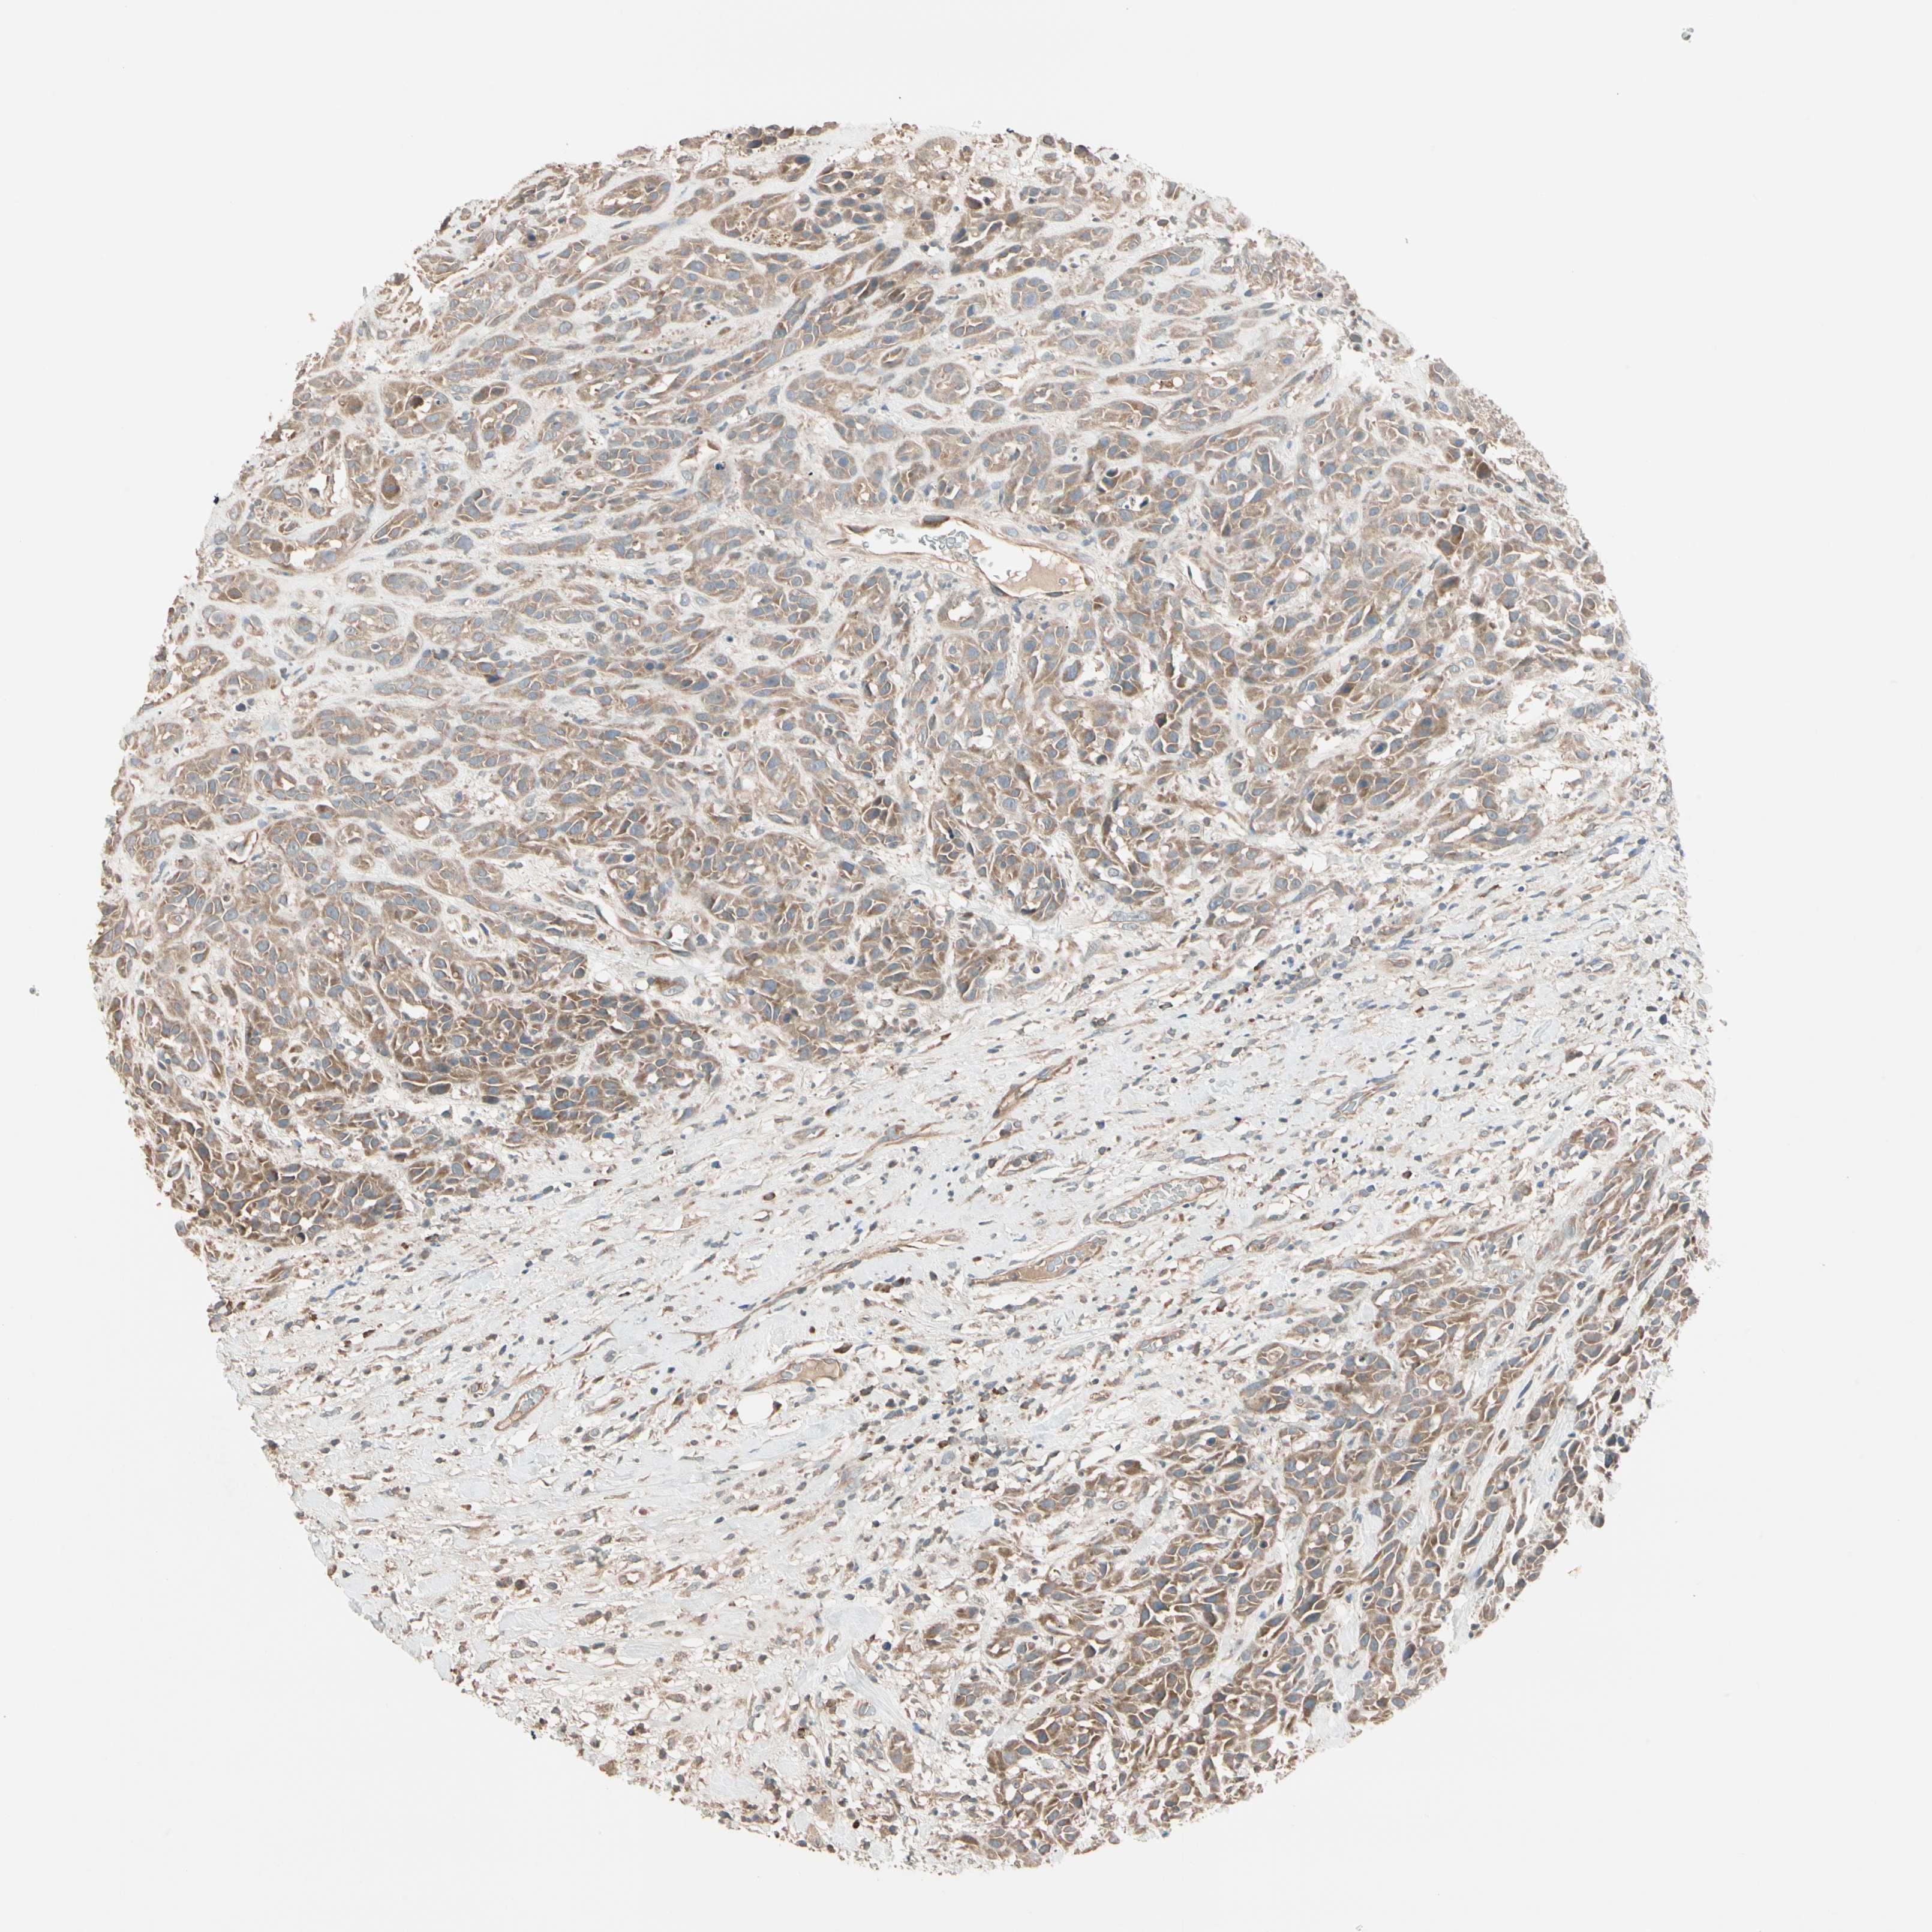

HEAD AND NECK CANCER - Protein expressioni

A mouse-over function shows sample information and annotation data. Click on an image to view it in a full screen mode. Samples can be filtered based on level of antibody staining by selecting one or several of the following categories: high, medium, low and not detected. The assay and annotation is described here.

Antibody stainingi

Antibody staining in the annotated cell types in the current human tissue is reported as not detected, low, medium, or high, based on conventional immunohistochemistry profiling in selected tissues. This score is based on the combination of the staining intensity and fraction of stained cells.

Each image is clickable and will lead to virtual microscopy that enables deeper exploration of all samples and also displays staining intensity scores, fraction scores and subcellular localization as well as patient and tissue information for each sample.

Antibody CAB009805

Staining

High

Medium

Low

Not detected

Intensity

Strong

Moderate

Weak

Negative

Quantity

>75%

75%-25%

<25%

None

Location

Nuclear

Cytoplasmic/membranous

Cytoplasmic/membranous,nuclear

Squamous cell carcinoma, NOS